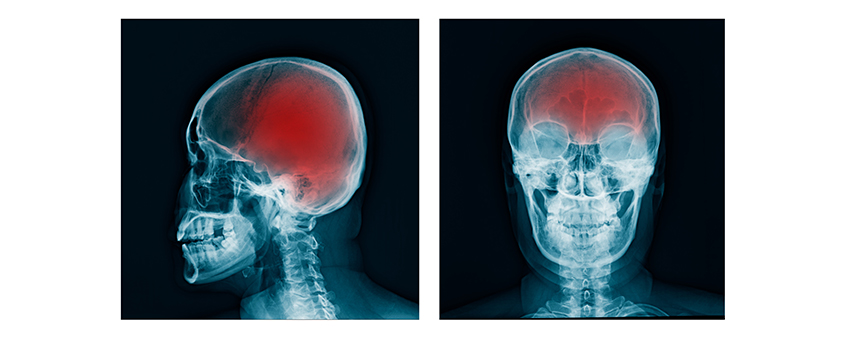

What Sports Are Most Likely to Cause a Traumatic Brain Injury? According to the Brain Trauma Foundation, more than 2.5 million people experience a traumatic brain injury (TBI) each year. While a TBI can happen during any sport, certain sports put an athlete at a...